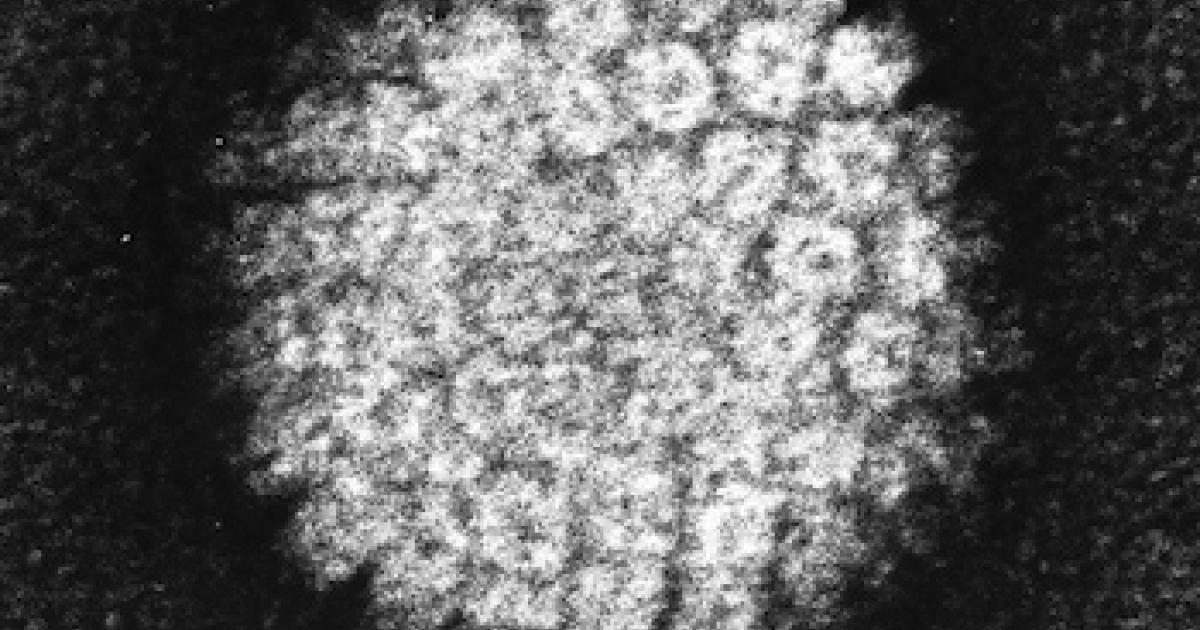

The human papillomavirus (HPV) comes in about 150 different varieties known as "strains." Some strains cause warts to grow on your feet, and this kind of HPV can be acquired by walking barefoot in moist areas, like public swimming pools or hotel showers. Other HPV strains are spread sexually, and these can cause genital warts or cancer.

The sexually transmitted HPV strains are very common. Indeed, they have been likened to the "common cold," and it is thought that 80% of sexually active people are infected with at least one HPV strain at some point in their lives. For most people, the virus is cleared, and they never even knew they were infected. But in some, the virus persists and causes cancer.

Several years ago, the FDA approved a nine-valent HPV vaccine, which means it targets nine different HPV strains (seven of which cause cancer and two of which cause genital warts). The vaccine is nearly 100% effective for preventing cervical infection (and hence, cervical cancer) by the HPV strains it targets.